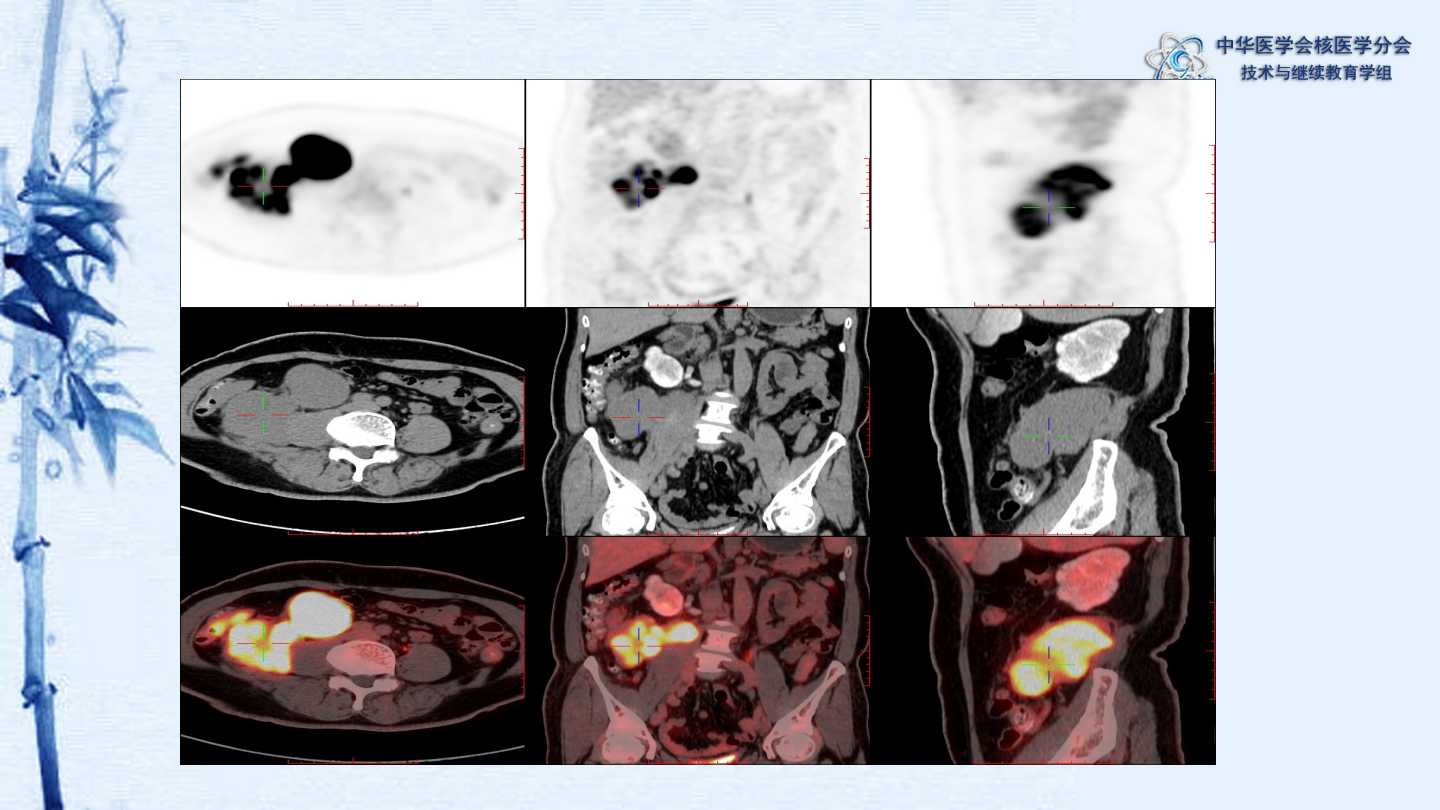

【CSNM继教学组】病例E51-邢岩-结肠炎性肌纤维母细胞瘤18F-FDG PET/CT显像